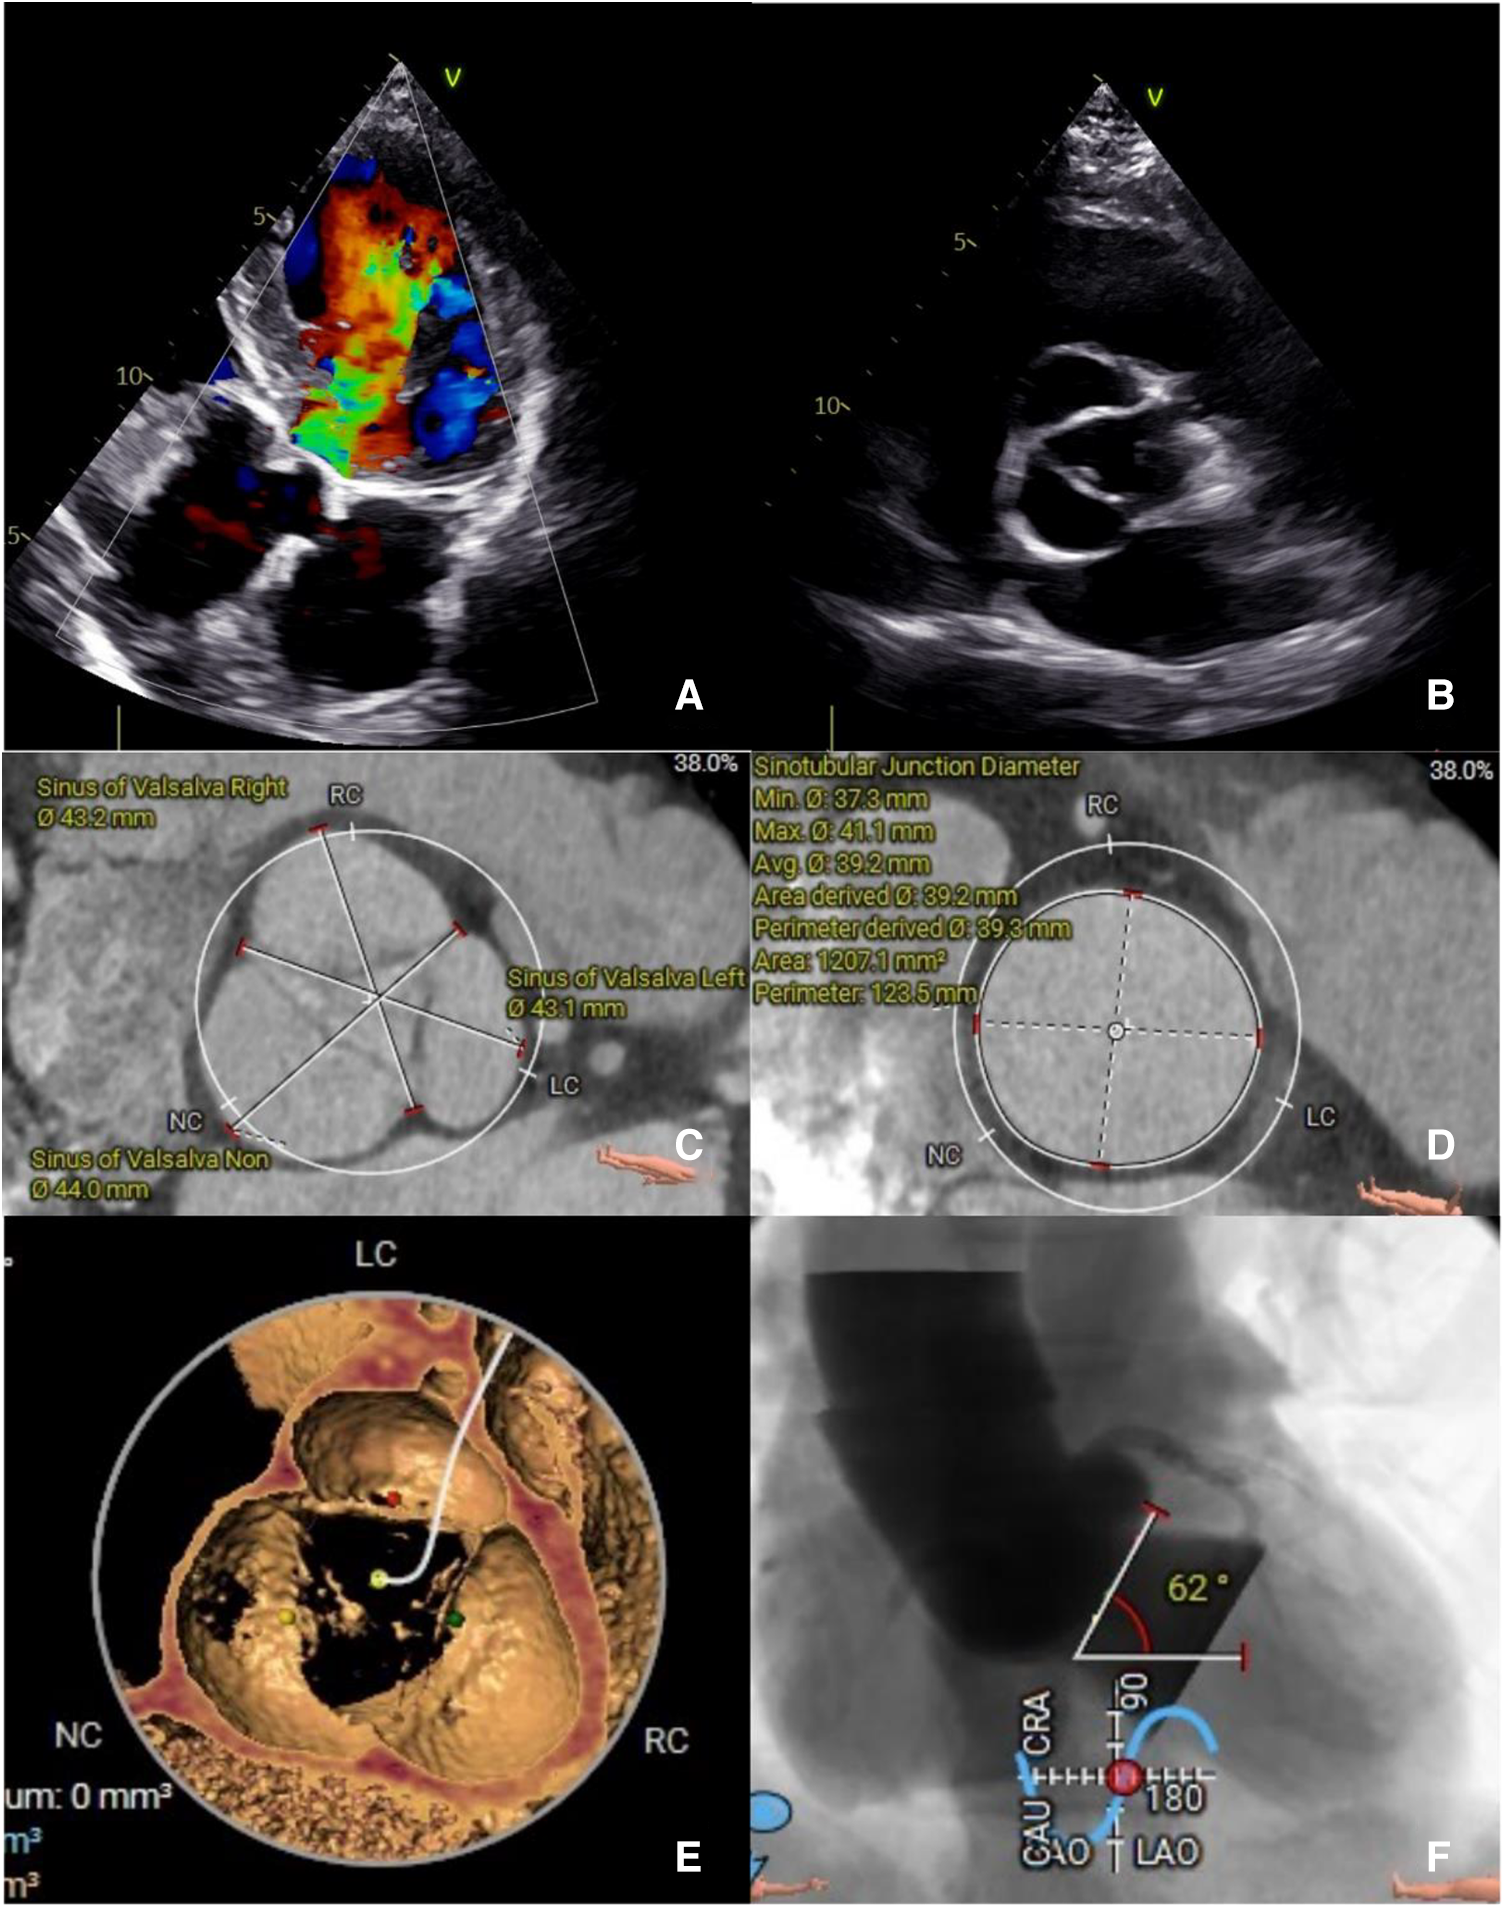

Figure 1

(A) The preoperative transthoracic echocardiogram in diastole showing severe AR and (B) absence of annulus and leaflets calcification. A preoperative computed tomography evaluation (C,D) showing a large sinus of Valsalva and sinus tubular junction. (E) No annulus of leaflets calcification. (F) Aortic angulation.

A computed tomography (CT) angiography revealed a dilated sinus of Valsalva, with an average diameter of 43.4 mm, and a sinotubular junction (STJ), with an average diameter of 39.2 mm. No calcification was observed in the annulus or leaflets, with the aortic annulus area measuring 489.7 mm² and the perimeter measuring 79.6 mm. The left ventricular outflow tract (LVOT) perimeter was 85 mm, and the maximal ascending aorta diameter was 44.9 mm. Assessment of the coronary arteries and the arterial iliofemoral system anatomy indicated suitability for the TAVR procedure. Notably, the aortic angulation was 62°, which increases the surgical complexity for a patient with PNAR (Table 1, Figure 1).